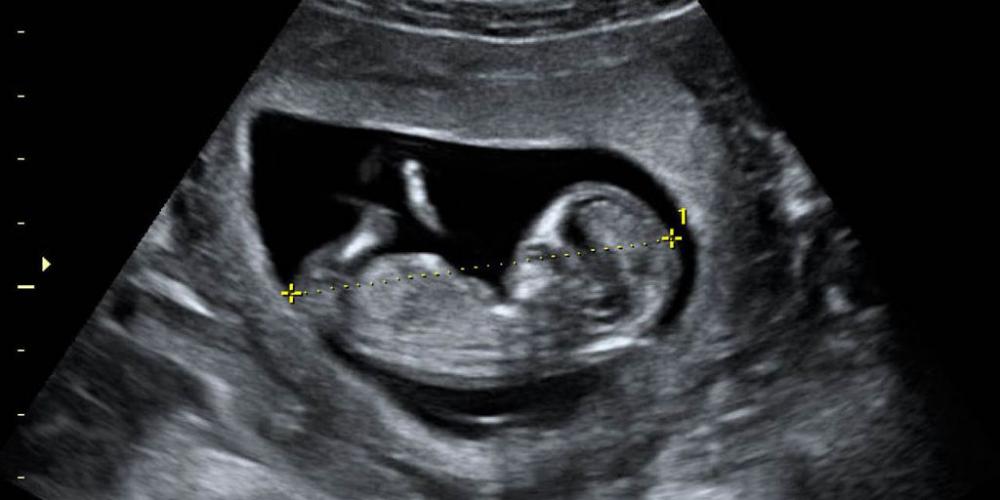

EN BUENOS AIRES MUEREN MÁS DE 90 NIÑOS ANTES DE NACER POR DÍA